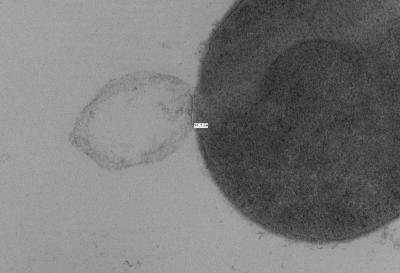

The balance between the bending and pressure forces led to the model prediction that holes 15 to 24 nanometers in diameter or larger would cause a bacteria cell to burst. To test the theory, Daniel Nelson, an assistant professor at the University of Maryland, used transmission electron microscopy images to measure the size of holes created in lysed Streptococcus pyogenes bacteria cells following PlyC exposure.

Nelson found holes in the lysed bacteria cells that ranged in diameter from 22 to 180 nanometers, with a mean diameter of 68 nanometers. These experimental measurements agreed with the researchers' theoretical prediction of critical hole sizes that cause bacterial cell death.